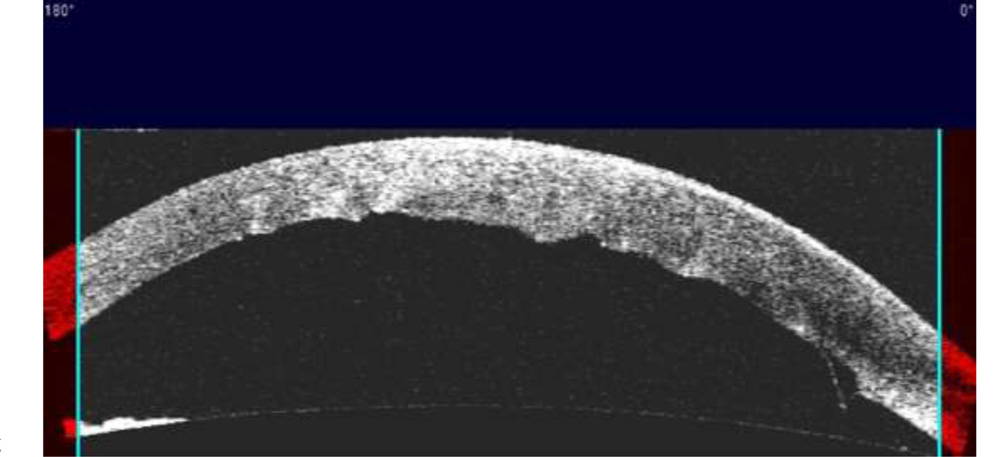

His surgery records revealed an uneventful phacoemulsification surgery for a white mature cataract. Striate keratopathy was noted in the immediate post-operative period. AS-OCT showed small DMD at the site of the incision, no DMD was noted elsewhere (Figure 3). The striate keratopathy had resolved completely over a period of 4 weeks with the best corrected vision of 6/6.

Figure 3: Day 1 post-operative AS-OCT image showing increase in corneal thickness, irregular DM and small DMD at the incision site.

Figure 4: Complete resolution of DMD with minimal DM scarring

DM can be seen corresponding to the scarred area (Arrow).

Figure 5: AS-OCT image confirming the resolution of DMD. Irregular